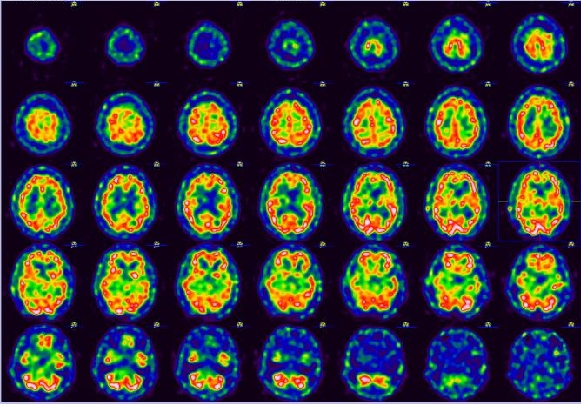

뇌 혈류 검사

4. 증례 영상

정상 뇌혈류 영상

뇌 경색 영상